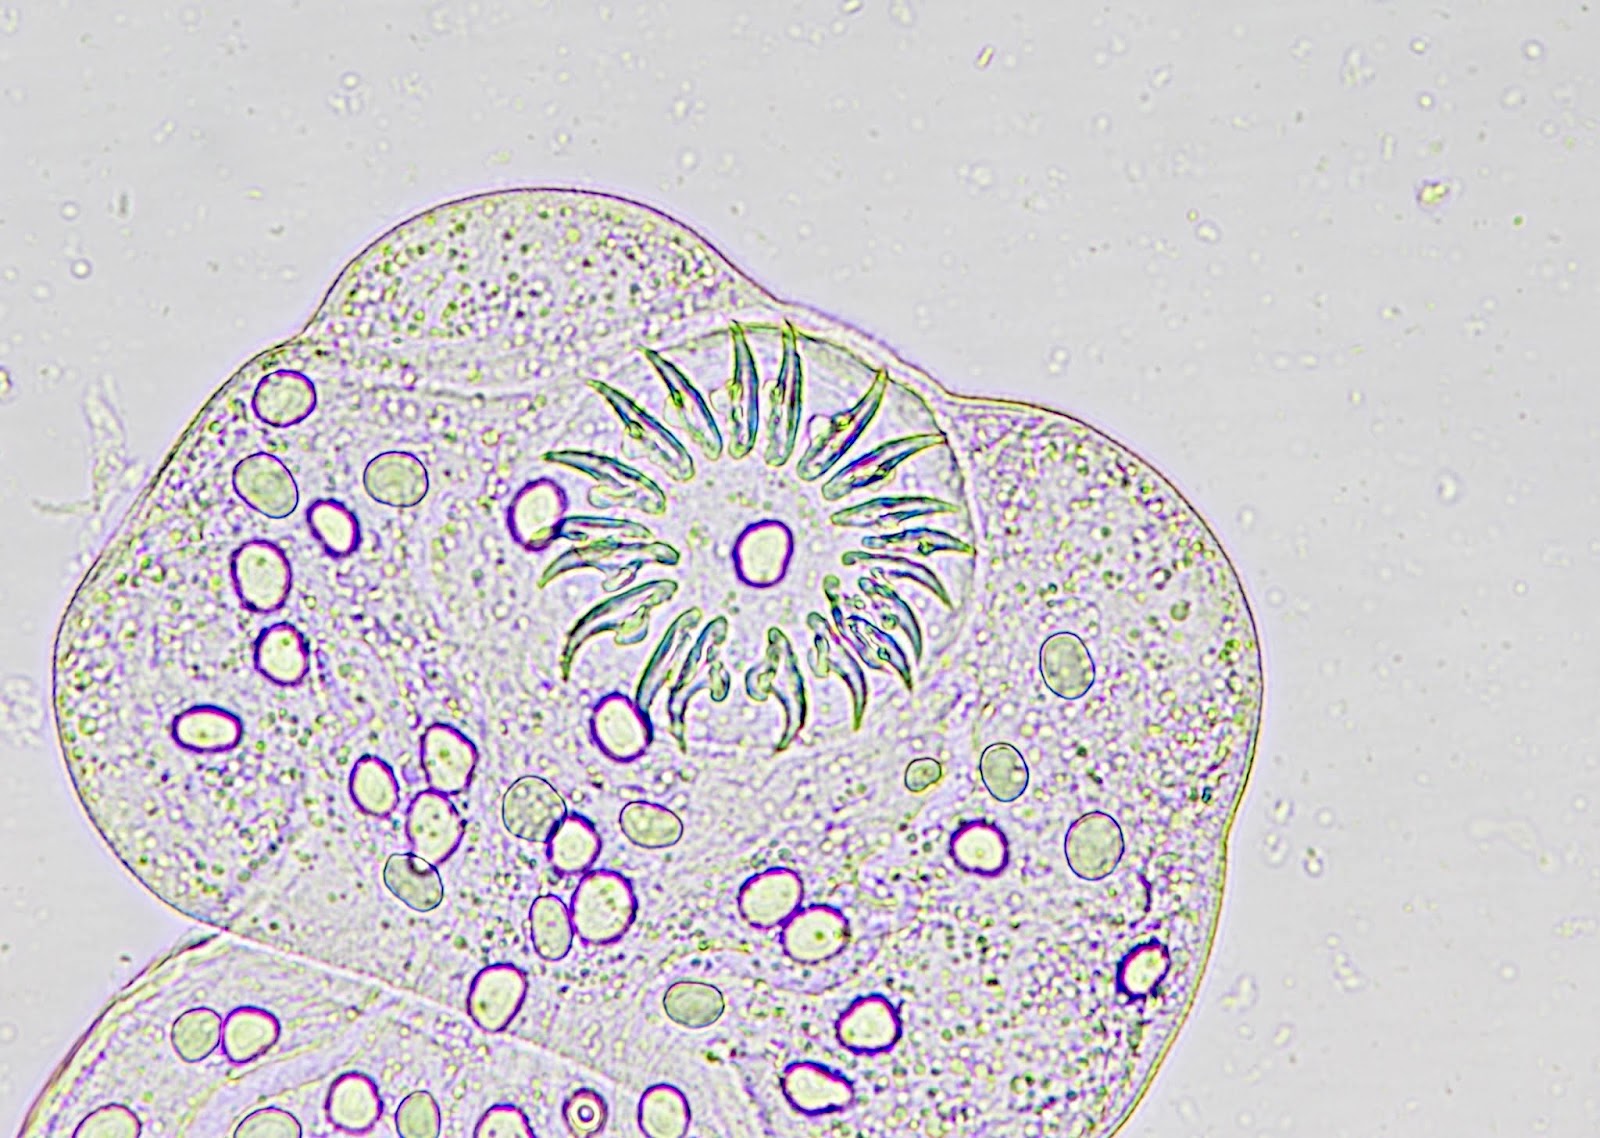

- Parasitic flatworm (tapeworm) of class Cestoda (i.e., a cestode) (Pritt: Creepy Dreadful Wonderful Parasites Blog - Answer to Case 514 [Accessed 4 March 2022])

- Member of family Taeniidae due to presence of an armed rostellum (i.e., 2 rows of hooklets) (Pritt: Creepy Dreadful Wonderful Parasites Blog - Answer to Case 514 [Accessed 4 March 2022])

- Protoscolices, attached to the membrane and budding from it

- Protoscolices are ovoid and contain hooklets (birefringent under polarized light) and a sucker

Microscopic (histologic) images

Positive stains

- Hooklets are acid fast positive on Ziehl-Neelsen stain; also stain with GMS (J Cytol Histol 2016;7:1000422)